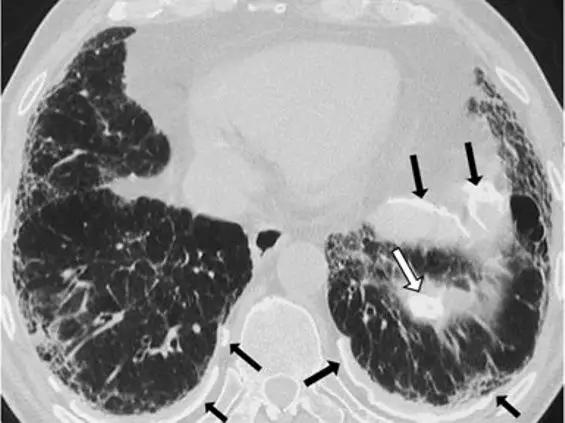

晚期结节病表现为类似IPF的纯网状模式,特征是小叶间隔增厚,小叶内线性混浊,牵引性支气管扩张和蜂窝状结节。支持结节病诊断的主要发现是中上肺为主,支气管血管束周围结节性增厚和对称淋巴结肿大,有时伴有钙化。

*晚期结节病。下叶水平的HRCT表现为粗大的“网状图案”,肺结构变形,胸膜下牵引支气管扩张和支气管扩张,支气管周围血管间质增厚和蜂窝状改变。